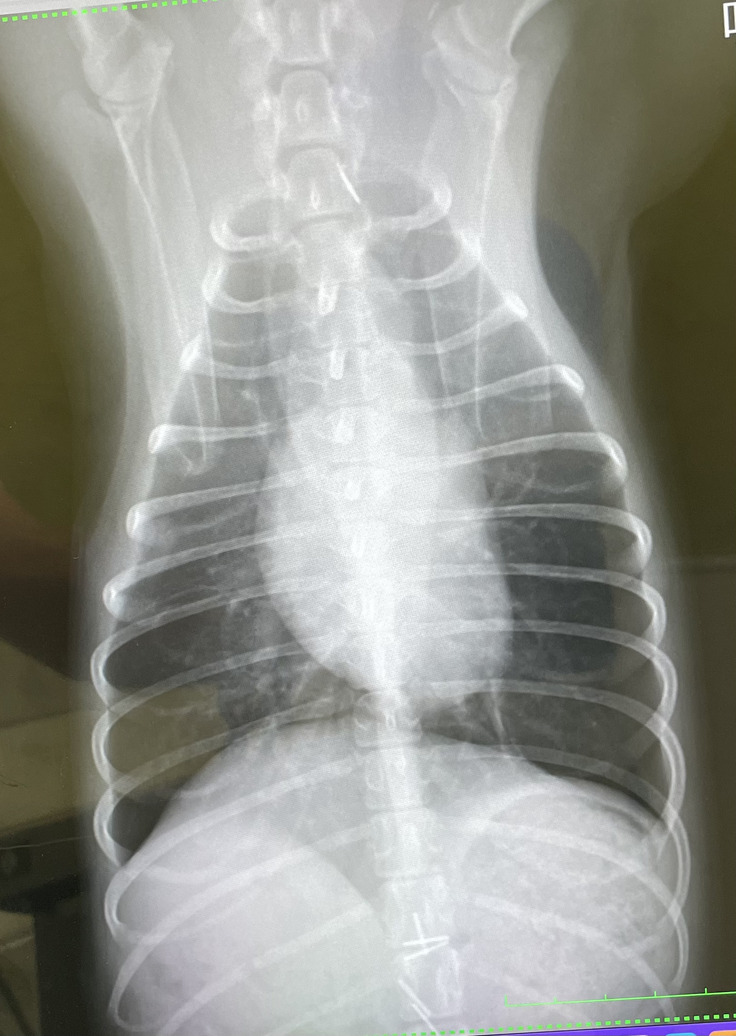

【一昨日のレントゲン】全体的に白かった部分がなくなり黒い部分が目立つように。

見比べると非常に改善していることが分かるようになりました。

最初は見えてしまっていた肺も見えなくなり、ほぼ正常な状態になってきました。

エコーでの確認では多少の胸水が見られるものの生理現象のレベルのようで順調に回復してきました。